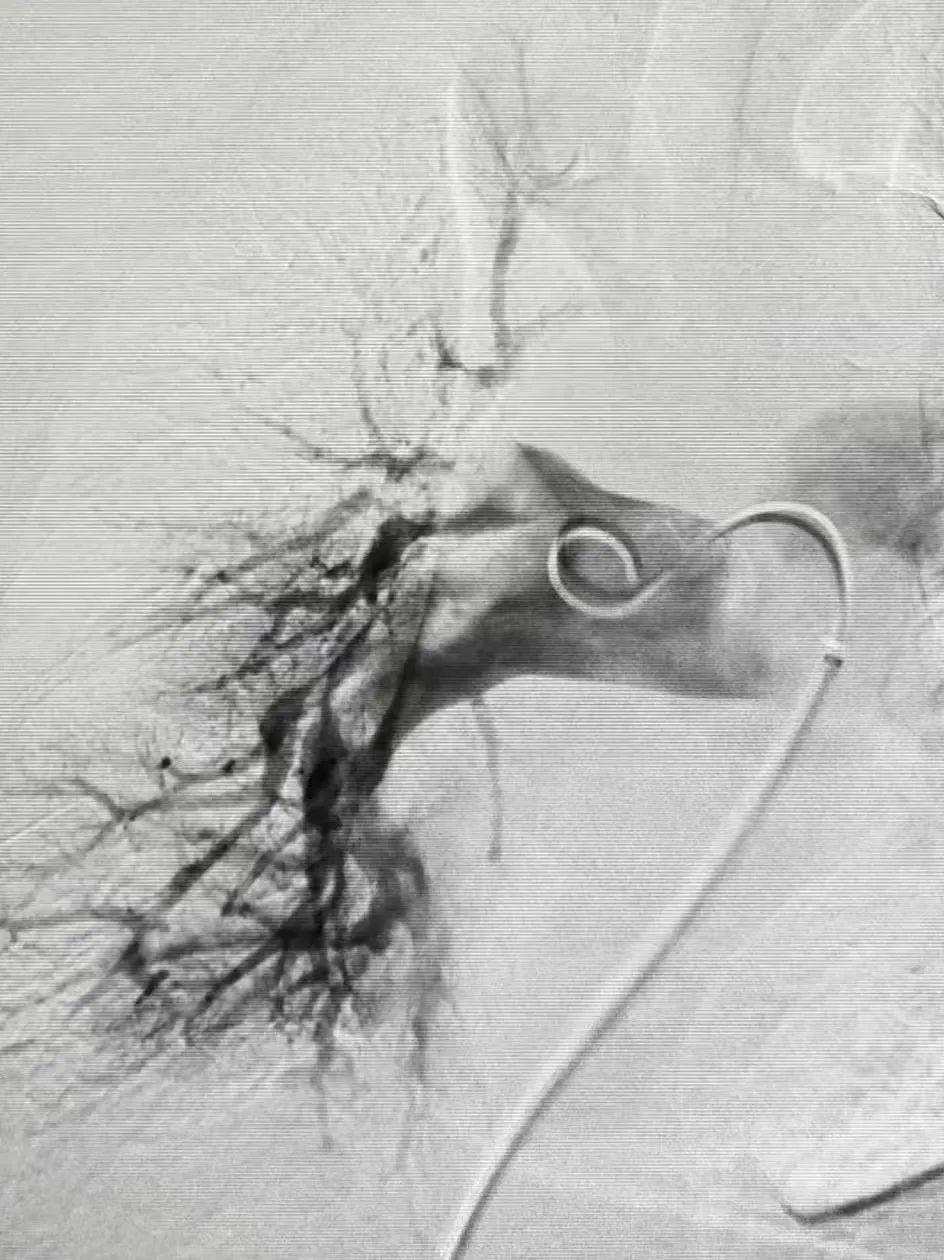

面对复杂的病情,团队成员紧密配合,无缝衔接,从检查诊断到手术治疗,每一个环节都严谨细致,确保了治疗的高效和安全,为患者的康复提供了有力保障。经导管血栓清除技术、肺动脉取栓系统等先进技术的应用,不仅提高了治疗效果,还降低了患者的痛苦和并发症的发生风险。